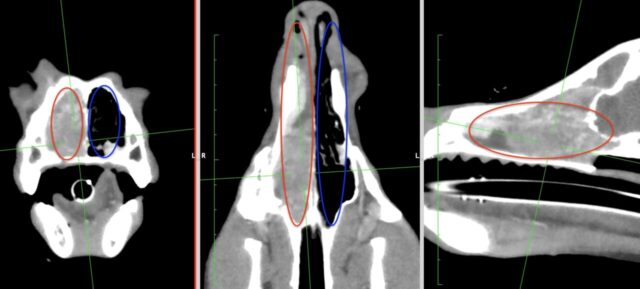

・CT検査:がんの大きさや広がり、リンパ節転移、遠隔転移の評価

※鼻腔内腺癌の場合、鼻腔内の組織生検を行う位置の確認、骨や眼窩、脳などへの浸潤の評価のため、CT検査は必須の検査です

鼻腔内腺癌のCT画像(赤丸:腫瘍のある鼻腔内、青丸:正常な鼻腔内)

・MRI検査:特に脳への浸潤の評価のために実施される場合があります